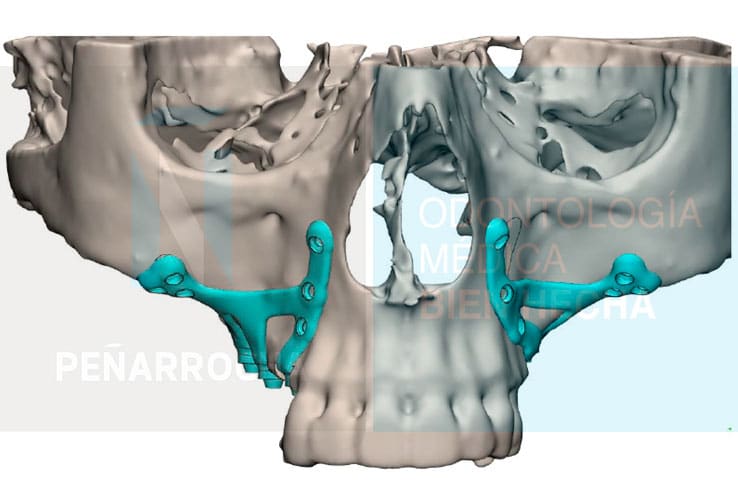

Aunque se colocan desde hace más de 50 años, la técnica ha evolucionado gracias a la odontología digital. Actualmente, se pueden diseñar y fabricar con mayor precisión mediante escáneres 3D o software CAD/CAM. Estas tecnologías innovadoras en el proceso de producción junto con la utilización de nuevos materiales y procedimientos de colocación, permiten obtener una adaptación perfecta a la anatomía de cada paciente y resultados mucho más predecibles.

Se diseñan y fabrican a medida mediante tecnología digital (CBCT, CAD/CAM, sinterización láser), lo que permite un ajuste preciso a la superficie del hueso maxilar y a la anatomía del paciente.

Antes de la cirugía se realiza un estudio individualizado de cada paciente mediante pruebas de imagen avanzadas como la tomografía computarizada (CBCT) y escaneados intraorales. Gracias a la mejora del diseño y la fabricación digital asistida por ordenador, podemos conocer al detalle la anatomía ósea y diseñar un plan de tratamiento personalizado para la colocación del implante yuxtaoseo.

3. Diseño personalizado del implante

Con la información obtenida del estudio, el equipo diseña de forma digital los implantes a medida y se planifica su posición sobre la pantalla del ordenador. A partir de este diseño, se fabrican unas férulas quirúrgicas que guiarán la colocación del implante subperióstico durante la cirugía, asegurando que la estructura se adapte perfectamente al hueso del paciente.